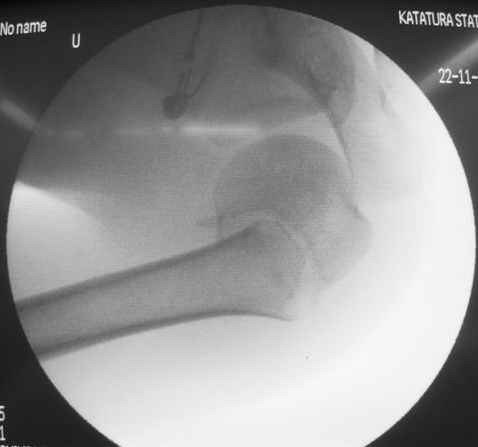

Пока я пользуюсь методикой принятой у нас (методика Сиэтла), также перкутанный спицевой метод, только сцицы 2.8 мм с резбой на конце.

Здесь случай перелома-вывиха плеча, больному 56 лет, после "дважды" закрытой неудачной репозиции, опять же ургентно взяли в операционную, после полного общего обезболивания попытались сделать репозицию, и фиксацию провели спицами.

Больной находился в повязке, примерно напоминяющей косыночную, рекомендованы движения в локтевом суставе и маятниковые движения в плече, спицы удалены в три недели (были случаи миграции)

Больной амбулаторный, предупрежден на случай осложнения АВН головки.